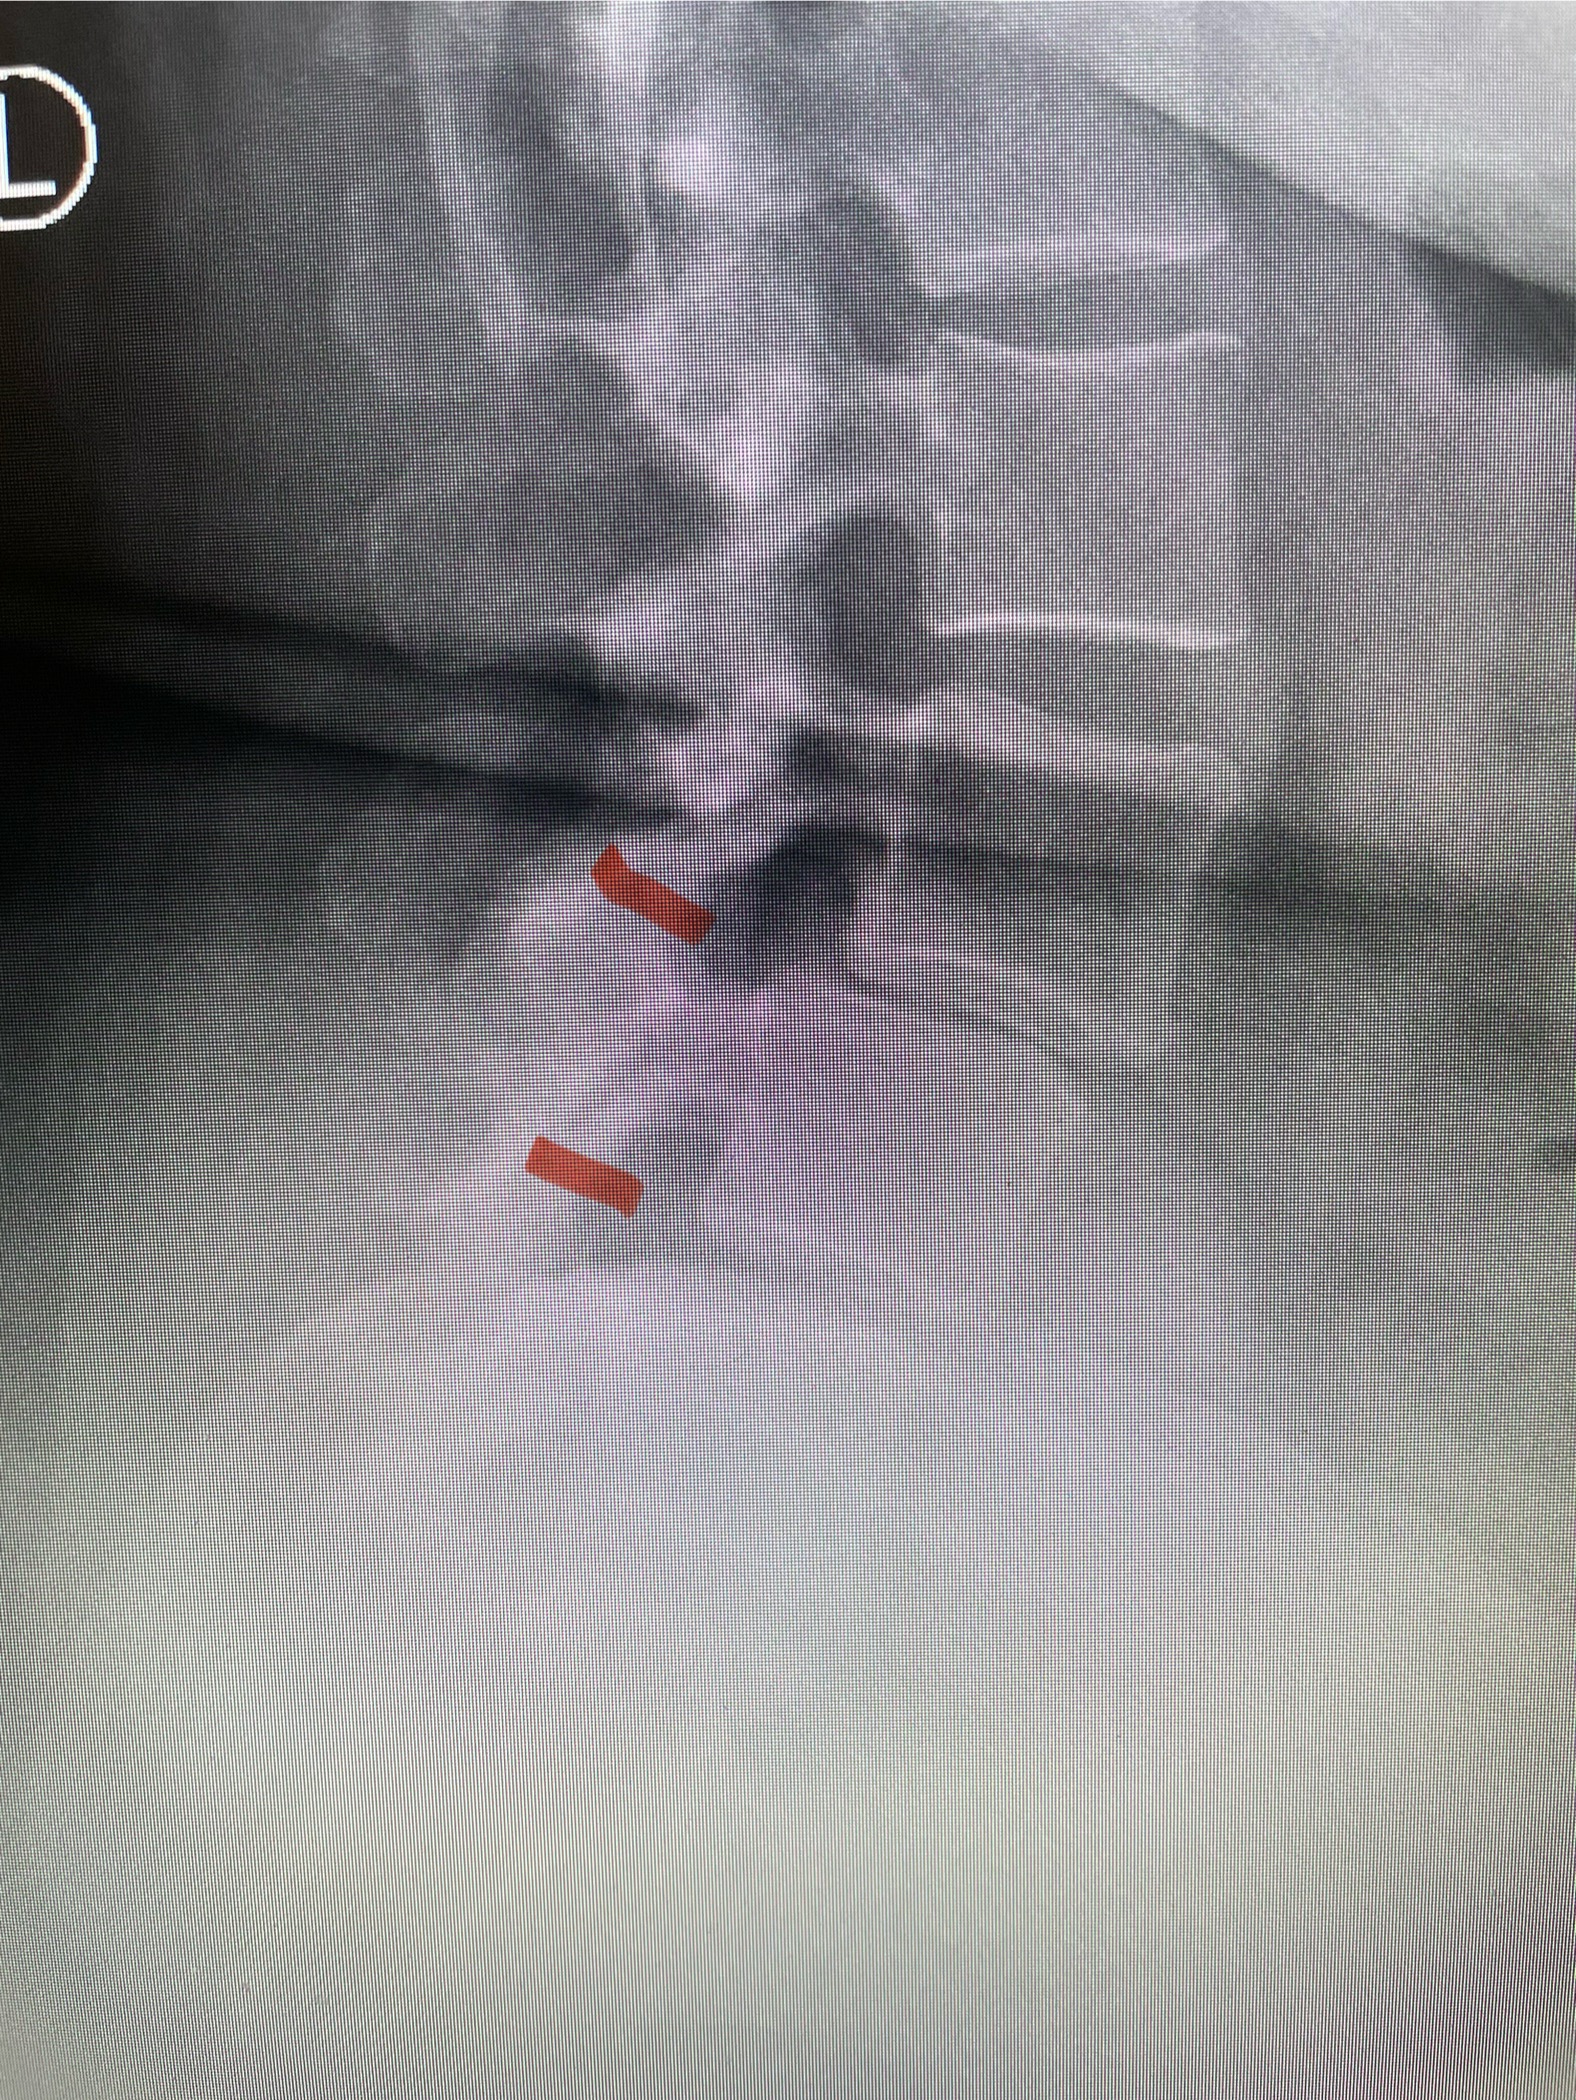

Fig 1b: axial T2-weighted MRI demonstrating severe lumbar stenosis (red arrow)